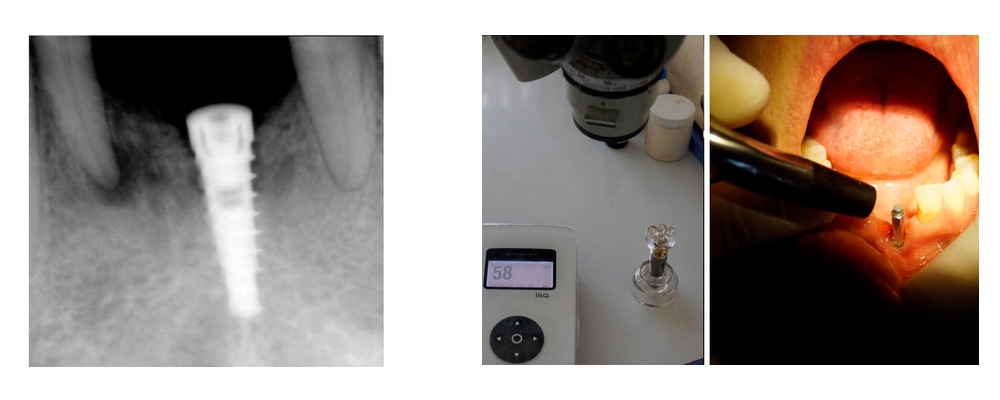

Tratamiento: La falta de espacio interproximal y la ausencia de hueso del reborde alveolar nos obliga a la colocación de un solo implante dental de titanio DSI con conexión interna hexagonal (3.75 de diámetro y 13.0 mm de longitud) sobre la línea media en la zona mentoniana, como lo muestra la radiografía periapical de la figura 3 y la clínica en la figura 4; la medición del OSSTELL aloja 58 ISQ a los 4 meses de la colocación del implante (fig. 5). Para la rehabilitación protésica se usa un pilar angulado a 17 grados como se muestra en la figura 6 y 7; en la radiografía de la figura 8 se muestra una corona de metal porcelana y dos pónticos para sustituir los centrales inferiores y la caracterización de la encía en porcelana (fig. 9).